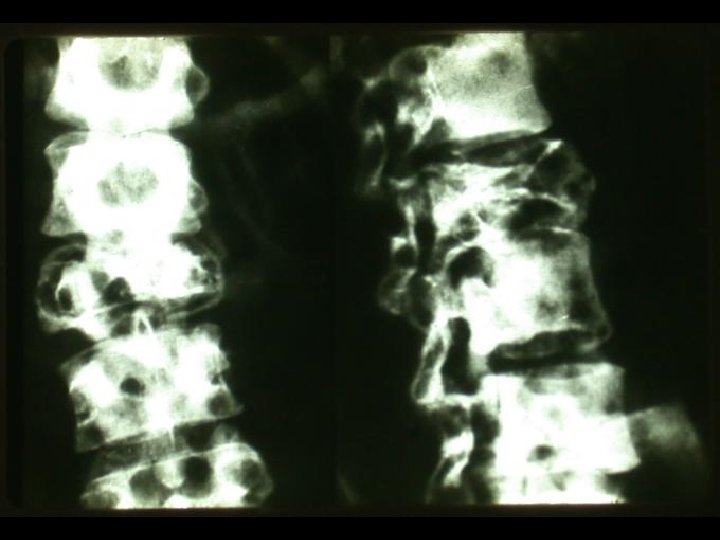

Caso 1 • Paciente masculino de 70 años, historia de dorsalgia que no responde

Caso 1 • Paciente masculino de 70 años, historia de dorsalgia que no responde a analgésicos, se agrega insuficiencia cardiaca. • Radiología de columna demuestra focos de destrucción ósea múltiples en cuerpos vertebrales. • Fallece por cuadro de descompensación cardiaca, en autopsia se confirma lesiones líticas de columna. • Se presenta histología y pesquisa de cadenas de inmunoglobulinas en foco lítico.